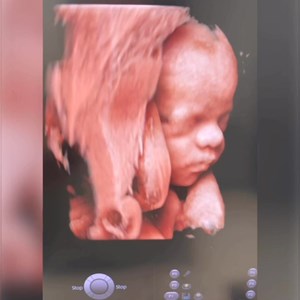

Når en 3D scanning bliver en magisk lille stund for den ventende familie 💞 Denne lille p...